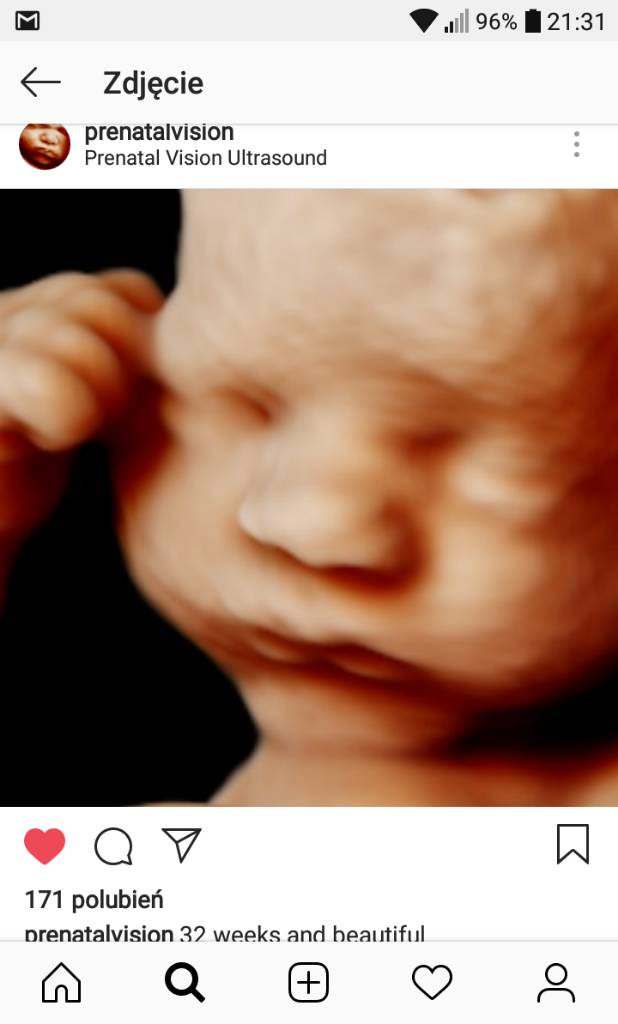

Co do fotek 3d to i Nicole Mamaginekolog wrzuca i mówi, że najładniej buzię widać ok. 30 tygodnia.

Obserwuję też na insta prenatalvision i wrzucę od nich foty. Zobacz sama. Tu 22 i 32 tydzień ciążyZobacz załącznik 878576Zobacz załącznik 878578Zobacz załącznik 878579Zobacz załącznik 878581

Rzeczywiście, piękne te fotki w okolicy 30tygodnia! Jak zdjęcie